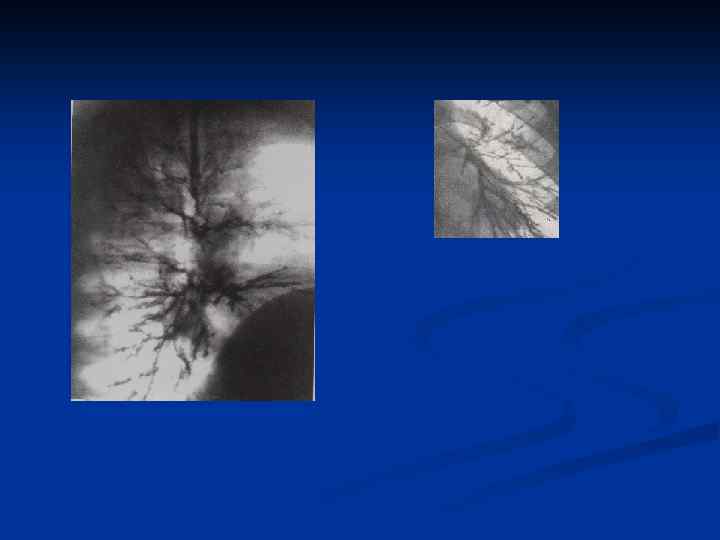

n При бронхографии на ранних стадиях развития хронического бронхита наблюдается фрагментированное заполнение и многочисленные обрывы контрастирования бронхов. Эти изменения обусловлены гиперсекрецией и свидетельствуют о наличии воспалительных изменений в стенках бронхов, не отражая тяжести их поражения.

n С прогрессированием болезни развивается деформирующий бронхит. Происходит умеренное расширение бронхов цилиндрического характера. Наблюдается неравномерность просвета бронхов за счет чередования участков расширения и сужения, в основе которого лежат рубцовые изменения бронхиальной стенки. Для хронического бронхита характерны также бронхиолоэктазии в виде мелких полостей диаметром 3– 5 мм. В дальнейшем деформирующий бронхит переходит в бронхоэктазы.